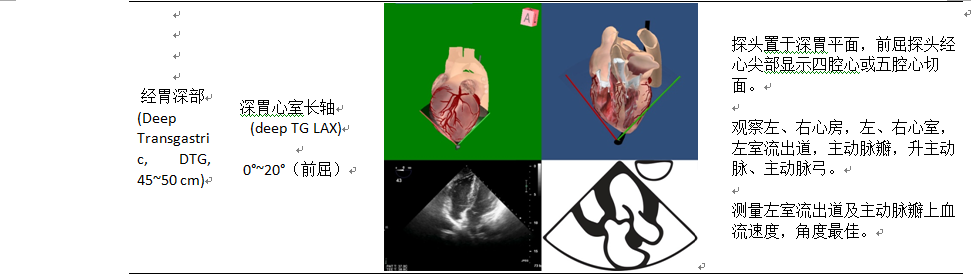

主动脉瓣体包括左心室流出道、主动脉瓣和主动脉根部。主动脉瓣超声评估的切面包括:经食管中段五腔心切面、经食管中段左室长轴切面、经食管中段主动脉瓣短轴和长轴切面、经胃底左室长轴切面、经深胃底五腔心切面。同时应该仔细评估主动脉瓣体是否存在潜在的主动脉下、主动脉和瓣膜上梗阻。熟悉所有这些结构是很重要的,因为任何水平的阻塞或扩张最终都会影响主动脉瓣的功能。